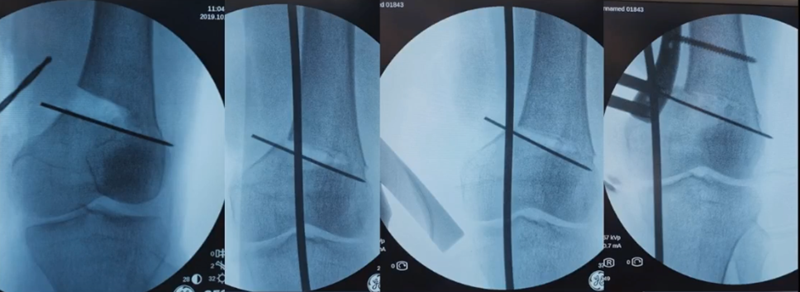

对于术中出现的合页骨折,此时还有一定的稳定性,可以调整力线固定以后,由前外向后内打一根防旋螺钉,这样仍然是比较稳定,术后康复计划与正常一样。

对于术中合页骨折,但非常不稳定、无法控制力线的情况,可以由外侧向股骨外髁打入一枚2.0的克氏针,因为克氏针具有一定弹性,相当于重建合页临时稳定性,在此基础上再去调整力线,做固定。

近端螺钉松开,调整力线,重新固定后,在外侧加小钢板抗旋。